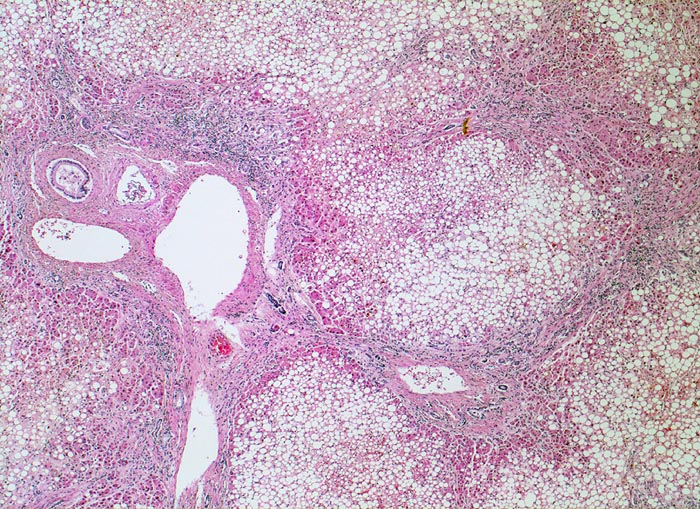

Die Steatose ist der früheste und häufigste pathologische Leberbefund ( 3260) und findet sich bei bis zu 90% der chronischen Alkoholiker. Nach Alkoholkarenz ist sie innerhalb von 3-4 Wochen reversibel. 20-40% der chronischen Alkoholiker entwickeln eine alkoholische Steatohepatitis (ASH). Die Steatohepatitis ist gekennzeichnet durch Schwellung und Ballonierung der Leberzellen, Nachweis von Mallory-Körperchen ( 4947), Apoptosen, perizelluläre Maschendrahtfibrose ( 4950) und überwiegend aus neutrophilen Granulozyten ( 4948)( 4949) bestehenden Entzündungsinfiltraten. Die Veränderungen sind bei Alkoholkarenz rückbildungsfähig. Bei etwa 50% der Patienten mit Steatohepatitis entwickelt sich eine Leberzirrhose ( 1095).

Gemischtes portales, septales und intralobuläres Entzündungsinfiltrat.

Floride sklerosierende alkoholische Steatohepatitis: Grobtropfige Verfettung von ca. 50% des Parenchyms.Neutrophile Granulozyten umgeben einzelne Hepatozyten (Satellitose). Wenig Apoptosekörperchen. Zahlreiche Mallory Körperchen und Megamitochondrien. Perivenuläre Maschendrahtfibrose.